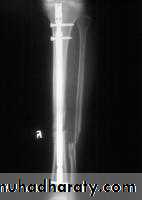

Operative treatment:

Indicated mainly when the fracture cannot be reduced adequately by manipulation, or when plaster alone fails to maintain an acceptable position of the fragments.Closed intramedullary nail or Plate and screws used commonly.

Fixations of fractures tibia and fibula